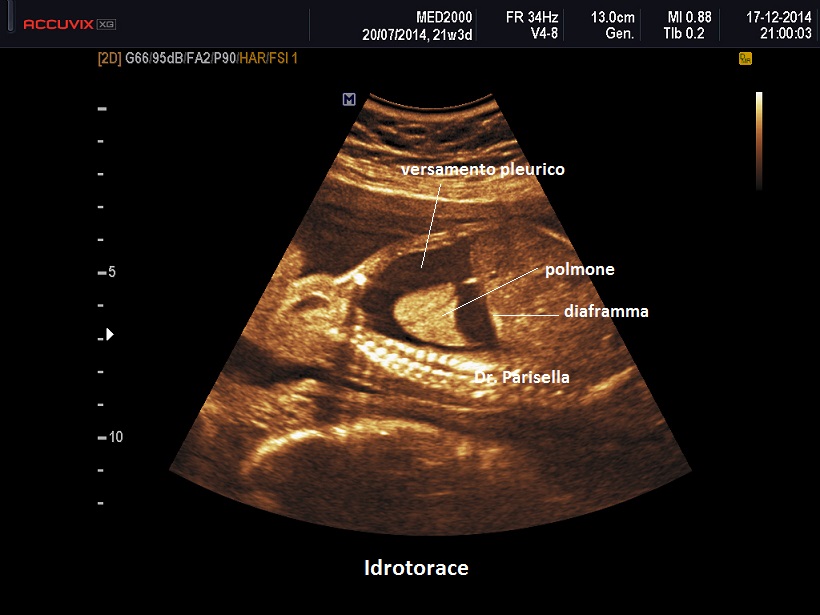

• effusione pleurica

Un primo orientamento sulle cause di idrope può essere fatto attraverso la localizzazione dell'accumulo di liquido: un accumulo generalizzato sin dal principio orienta verso una causa sistemica come l'anemia, mentre un accumulo inizialmente localizzato porta ad orientarsi verso una patologia locale ( es.: versamento pleurico >>>> Malformazione Adenomatoide Cistica Congenita del polmone).